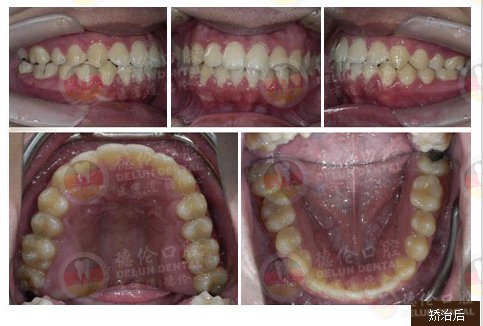

男 17岁

牙齿症状:下颌右侧第二、第三磨牙水平阻生,下颌左侧第三磨牙水平阻生

矫治方法:下颌拔除两颗第三磨牙(智慧齿)

发表于全球口腔正畸学界著名杂志J.Clin.Orthod